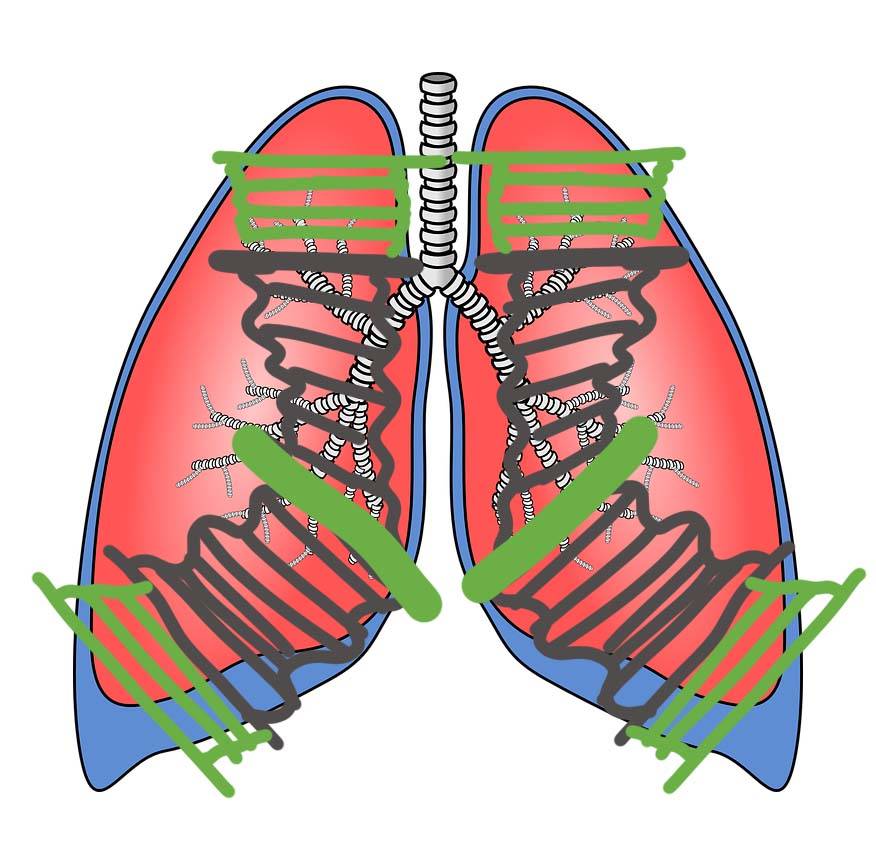

Теперь для наглядности представим что каждое легко состоит из нескольких частей.

Нижняя доля каждого лёгкого схематично представляет из себя гармошку с фиксированной стороной ближе к центру тела. Раздвигайте легочную гармошку во время каждого вдоха в стороны, чтобы усилить дыхание нижними долями легких. Научитесь дышать чтобы это происходило автоматически.

Средняя (для правого легкого) и верхняя доля легкого схематично представляется вертикально расположенной гармошкой с фиксированной нижней частью. Раздвигайте гармошку во время вдоха вверх и немного вперёд, чтобы активировать дыхание средней и верхними долями легких.

Мы не можем почувствовать непосредственно легкие или работу отдельных мышечных волокон диафрагмы. Но по движению живота, спины, рёбер можно сформировать образ того, что происходит с органами дыхания

Так например при ограничении расширения нижних легочных долей мы не почувствуем достаточного расширения нижних рёбер по направлению в стороны и к спине. Поэтому знание об анатомии и физиологическом движении позволяют понять как функционирует собственное тело.

Обратите внимание на грудную клетку. Насколько раскрываются нижние рёбра во время вдоха. Это дыхание будет соответствовать нижним долям легких. Насколько поднимается верхушка грудины и верхние рёбра. Это дыхание соответсвует средним и верхним долям легких.